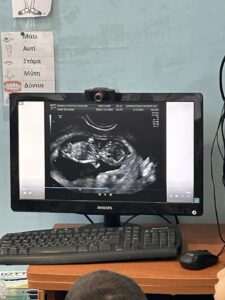

Η δραστηριότητα αυτή έχει ως στόχο να γνωρίσουν τα παιδιά τη διαδικασία του υπερηχογραφήματος και να κατανοήσουν πώς οι γιατροί χρησιμοποιούν αυτή την τεχνολογία για να δουν το μωρό μέσα στην κοιλιά της μαμάς. Μέσα από την παρακολούθηση μιας εικόνας υπερήχου στον υπολογιστή, τα παιδιά παρατηρούν και αναγνωρίζουν τα βασικά σημεία του σώματος του μωρού, δίνοντας έμφαση στα οστά που είναι ορατά.

- Τα παιδιά παρακολουθούν στον υπολογιστή μια εικόνα υπερήχου που δείχνει το μωρό μέσα στη μήτρα.

- Στη συνέχεια, γίνεται εξήγηση για το τι είναι ο υπέρηχος και πώς μας βοηθά να βλέπουμε τα οστά και τα μέρη του σώματος του μωρού.